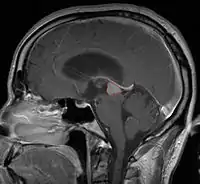

Pineal Gland Tumors

- Determined by the spatial anatomy and direction of growth

- Obstruction of aquaduct: hydrocephalus presenting as headaches, nausea, vomiting

- Compromise of superior colliculus: vertical gaze palsy, pupillary and oculomotor nerve paresis (Parinaud syndrome)

- Progressive growth: cranial nerve neuropathies, hypothalamic dysfunction

- Work-up includes MRI, CSF, serum markers for bHCG and AFP